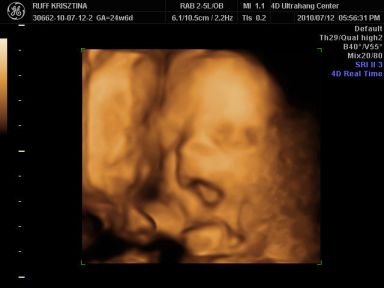

Kri: Brig nagyon cukorfalat a képeken, láccik jol érezte magát. Neked is medence fekvésű volt legutobb? Azt állitolag lehet a mozgásán is lehet érezni hogy merre van. Aztán kitudja...

Cherryke: nagyon édes a kis krapek !!

És neki é tök jol kivehető mindene, de olyan megtévesztő ilyenkor hogy kire hasonlit